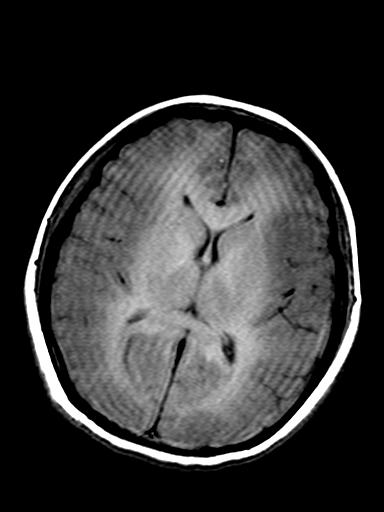

发热、头痛伴精神异常1周

较对称性脑白质异常信号,深部白质t2明显低信号(铁质沉积过多?)

考虑脑白质病变,请结合临床病史及实验室检查进一步分析。

f 23岁